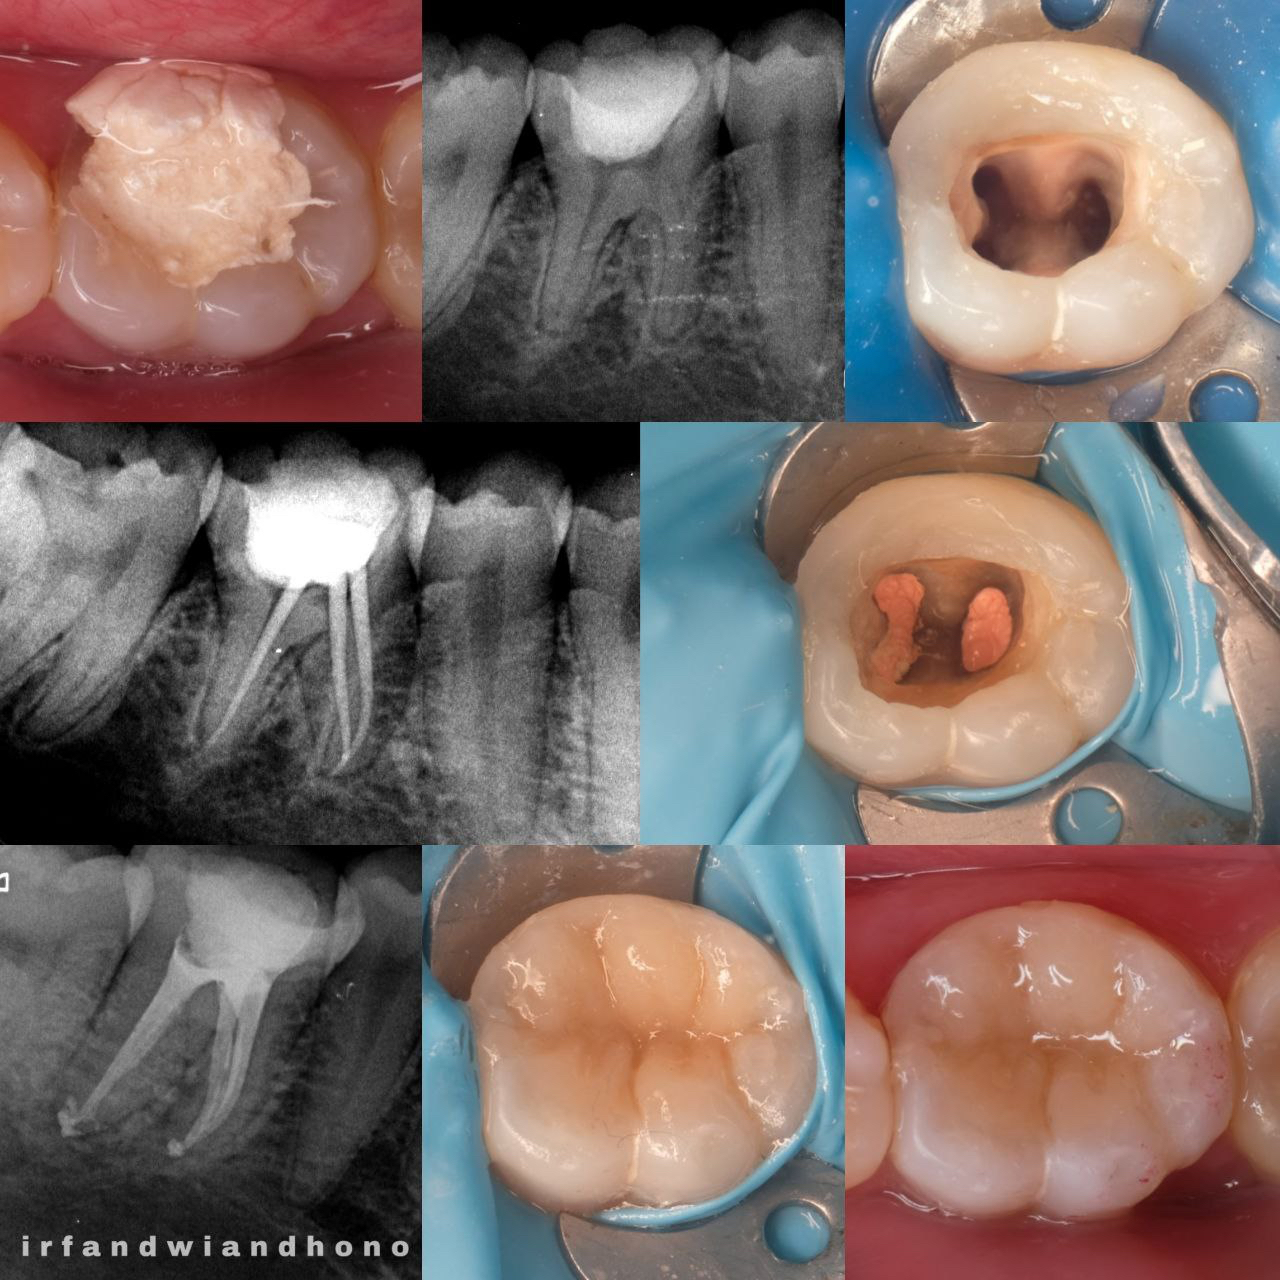

Prosedur untuk mengobati infeksi atau kerusakan pada pulpa gigi dengan membersihkan, mendisinfeksi, dan menutup saluran akar untuk menyelamatkan gigi dari pencabutan.

Spesialis Konservasi Gigi adalah cabang spesialistik kedokteran gigi yang mengatasi kelainan jaringan keras gigi, pulpa, periapikal, dengan cara melakukan perawatan gigi untuk mengembalikan fungsi stomatognatik, estetik, dan mempertahankan gigi selama mungkin di dalam rongga mulut